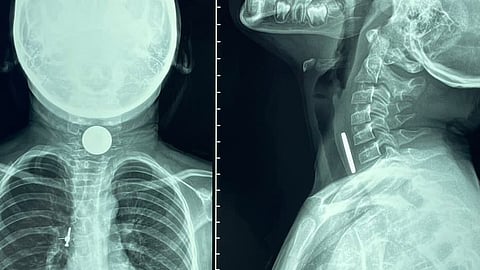

كانت صحة الجوف أعلنت أمس الإثنين، أن فريقا طبيا في مستشفى الأمير متعب بن عبدالعزيز بسكاكا، تمكن من إنقاذ مصاب في حادث مروري من فقد الحركة، بعد تدخل جراحي لفك الضغط على الحبل الشوكي.

وأوضحت صحة الجوف، أنه تبين بعد التشخيص إصابة المريض لكسر متفتت في الفقرة القطنية الأولى، وكسر متفتت آخر في الفقرة القطنية الثالثة، أدى إلى ضغط على الحبل الشوكي، مع تهديد واضح بفقدان الحركة في الطرفين السفليين.

وأشارت إلى أن المصاب استعاد القدرة على الحركة كاملة بصورة تامة بعد 42 ساعة من إجراء الجراحة، وتثبيت للفقرات بواسطة عشرة مسامير. وقضبان من مادة التيتانيوم.